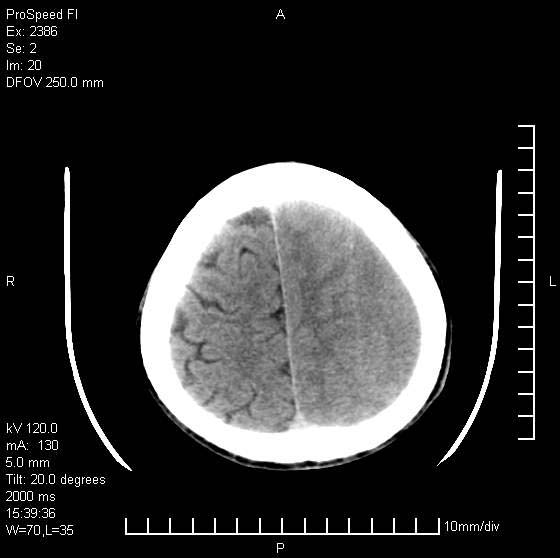

以下是引用天南地北在2007-9-19 18:43:00的发言:[br]典型慢性硬膜外血肿[br][br][本贴已被 天南地北 于 2007-9-19 18:44:11 修改过]

以下是引用曼一拍在2007-9-20 11:06:00的发言:[br]支持慢性硬膜下血肿.[br]慢性硬膜下积液:血肿有包膜,ct值稍高于脑脊液,增强可有染色。不典型者血肿可多呈梭形.是硬脑膜与蛛网膜之间的潜在腔隙内的血肿。[br]鉴别:[br]1\\硬膜外血肿:是颅脑外伤后脑膜或板障内血管破裂,血液在颅骨与硬膜之间积聚所致.通常是脑膜动脉破裂,也可因静脉窦破裂或颅骨的板障静脉出血,发生于外伤的着力部,常与颅骨骨折并存。脑膜动脉出血则急,若是板障静脉出血在则可有慢性。[br]2\\硬膜下积液:(硬膜下水瘤)[br]是由于蛛网膜破裂,脑脊液经蛛网膜破口进入硬膜下腔不能回流。或水肿阻塞而形成。[br]ct表现:颅骨内板下方新月形低密度区近似脑脊液密度;占位效应清,周围无脑水肿。[br]